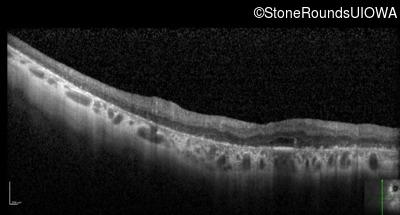

Optical Coherence Tomography - Right - Hand Motion

Exemplar / OCT Stack

OCT Stack